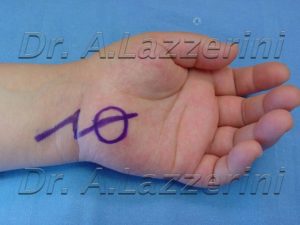

Dopo un intervento di neurolisi del mediano al canale carpale eseguito con tecnica endoscopica, la paziente ha presentato una sofferenza del nervo ulnare associata ad una massa pulsante e lievemente dolente in regione ipotenare.

Una arteriografia ha dimostrato la presenza di una dilatazione aneurismatica dell’arteria ulnare al palmo, verosimilmente causata dalla manovra chirurgica. L’asportazione dell’aneurisma con anastomosi diretta dell’arteria ha determinato la scomparsa dei disturbi.